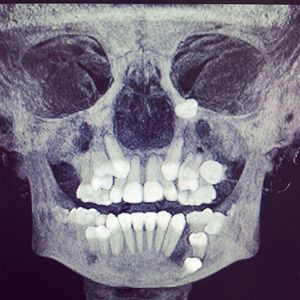

It seems like teeth can grow anywhere in the face doesn't it? ! π€·ββοΈπ€π Impacted teeth can exist as low or high in the jaws as you can imagine, even by the eye ! ππππ€π β’Such extreme impactions are usually associated with pathologic lesions within the maxilla and mandible . π€π·

Unbelievable case in this case if u take out all the extra Tooth's with is not so important in humans life will there grow again at the same place or we need to distory the cells completely, hw did it grow toward the eye need to take out almost 11Tooth's out and fix tow jows left lower and upper Jow